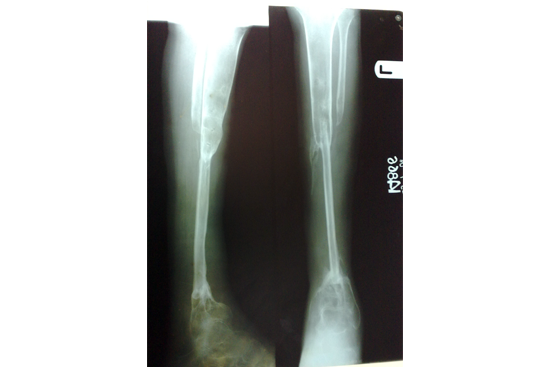

Tibialisation of Fibula

Method

We have done Huntington technique by stage ilizarov procedure. Here is the diagrammatic representation of our method.